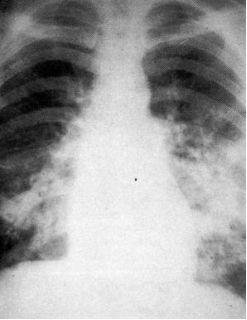

典型患者有心脏病,突发气促,咳粉红色泡沫痰,典型影像学如下